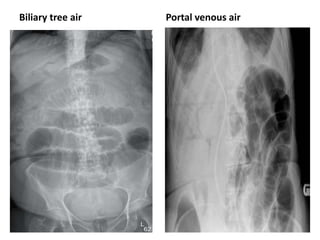

Gallstone ileus

• 2% of SBO

• Specific radiological signs in 40%

• High operative mortality

• Features

– Branching pattern of gas n biliary tree

– Gas in portal vein (peripheral)

– Obstructing gallstone in ileum

• Obscured by sacrum/overlying dilated gut

Biliary tree air Portal venous air

Gallstone ileus • 2%of SBO • Specific radiological signs in 40% • High operative mortality • Features – Branching pattern of gas n biliary tree – Gas in portal vein (peripheral) – Obstructing gallstone in ileum • Obscured by sacrum/overlying dilated gut

Biliary tree airPortal venous air